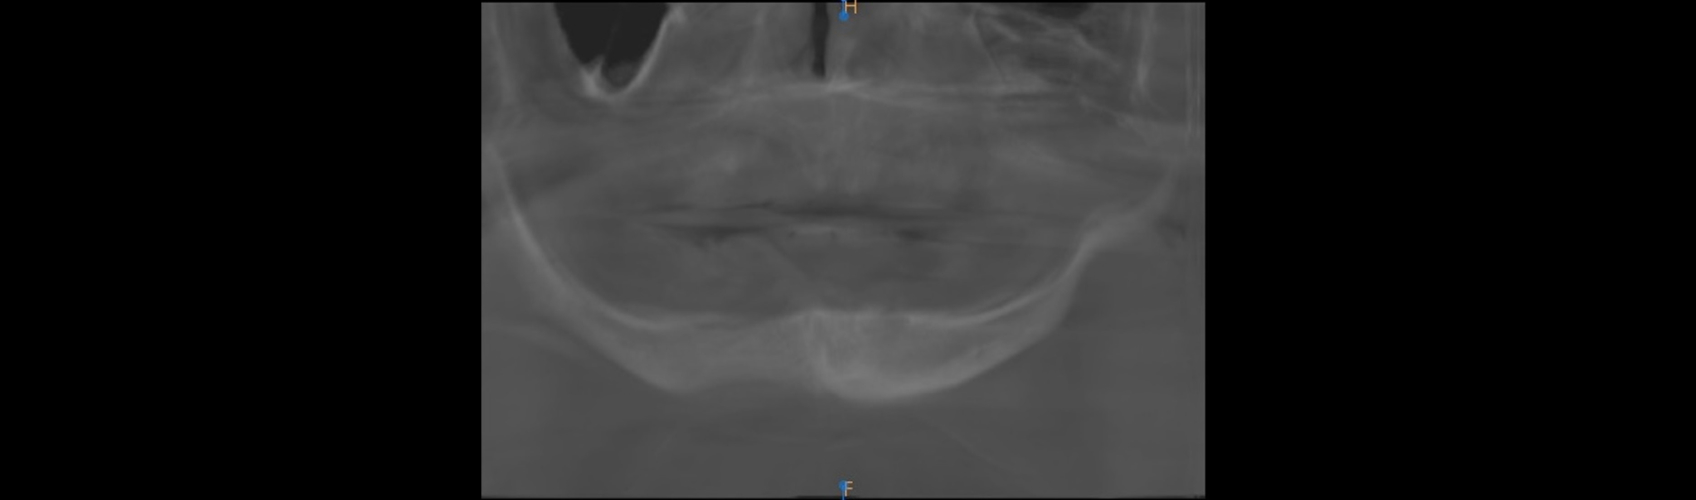

The patient expressed interest in implants to help retain or support new prostheses, and upon initial clinical exam, it appeared this might be a possibility on the upper arch but very unlikely on the lower. However, a follow-up CBCT (Fig. 21) revealed that the patient’s upper arch was a poor candidate for implants, while the lower arch could allow for implants mesial to the mental foramen on each side.